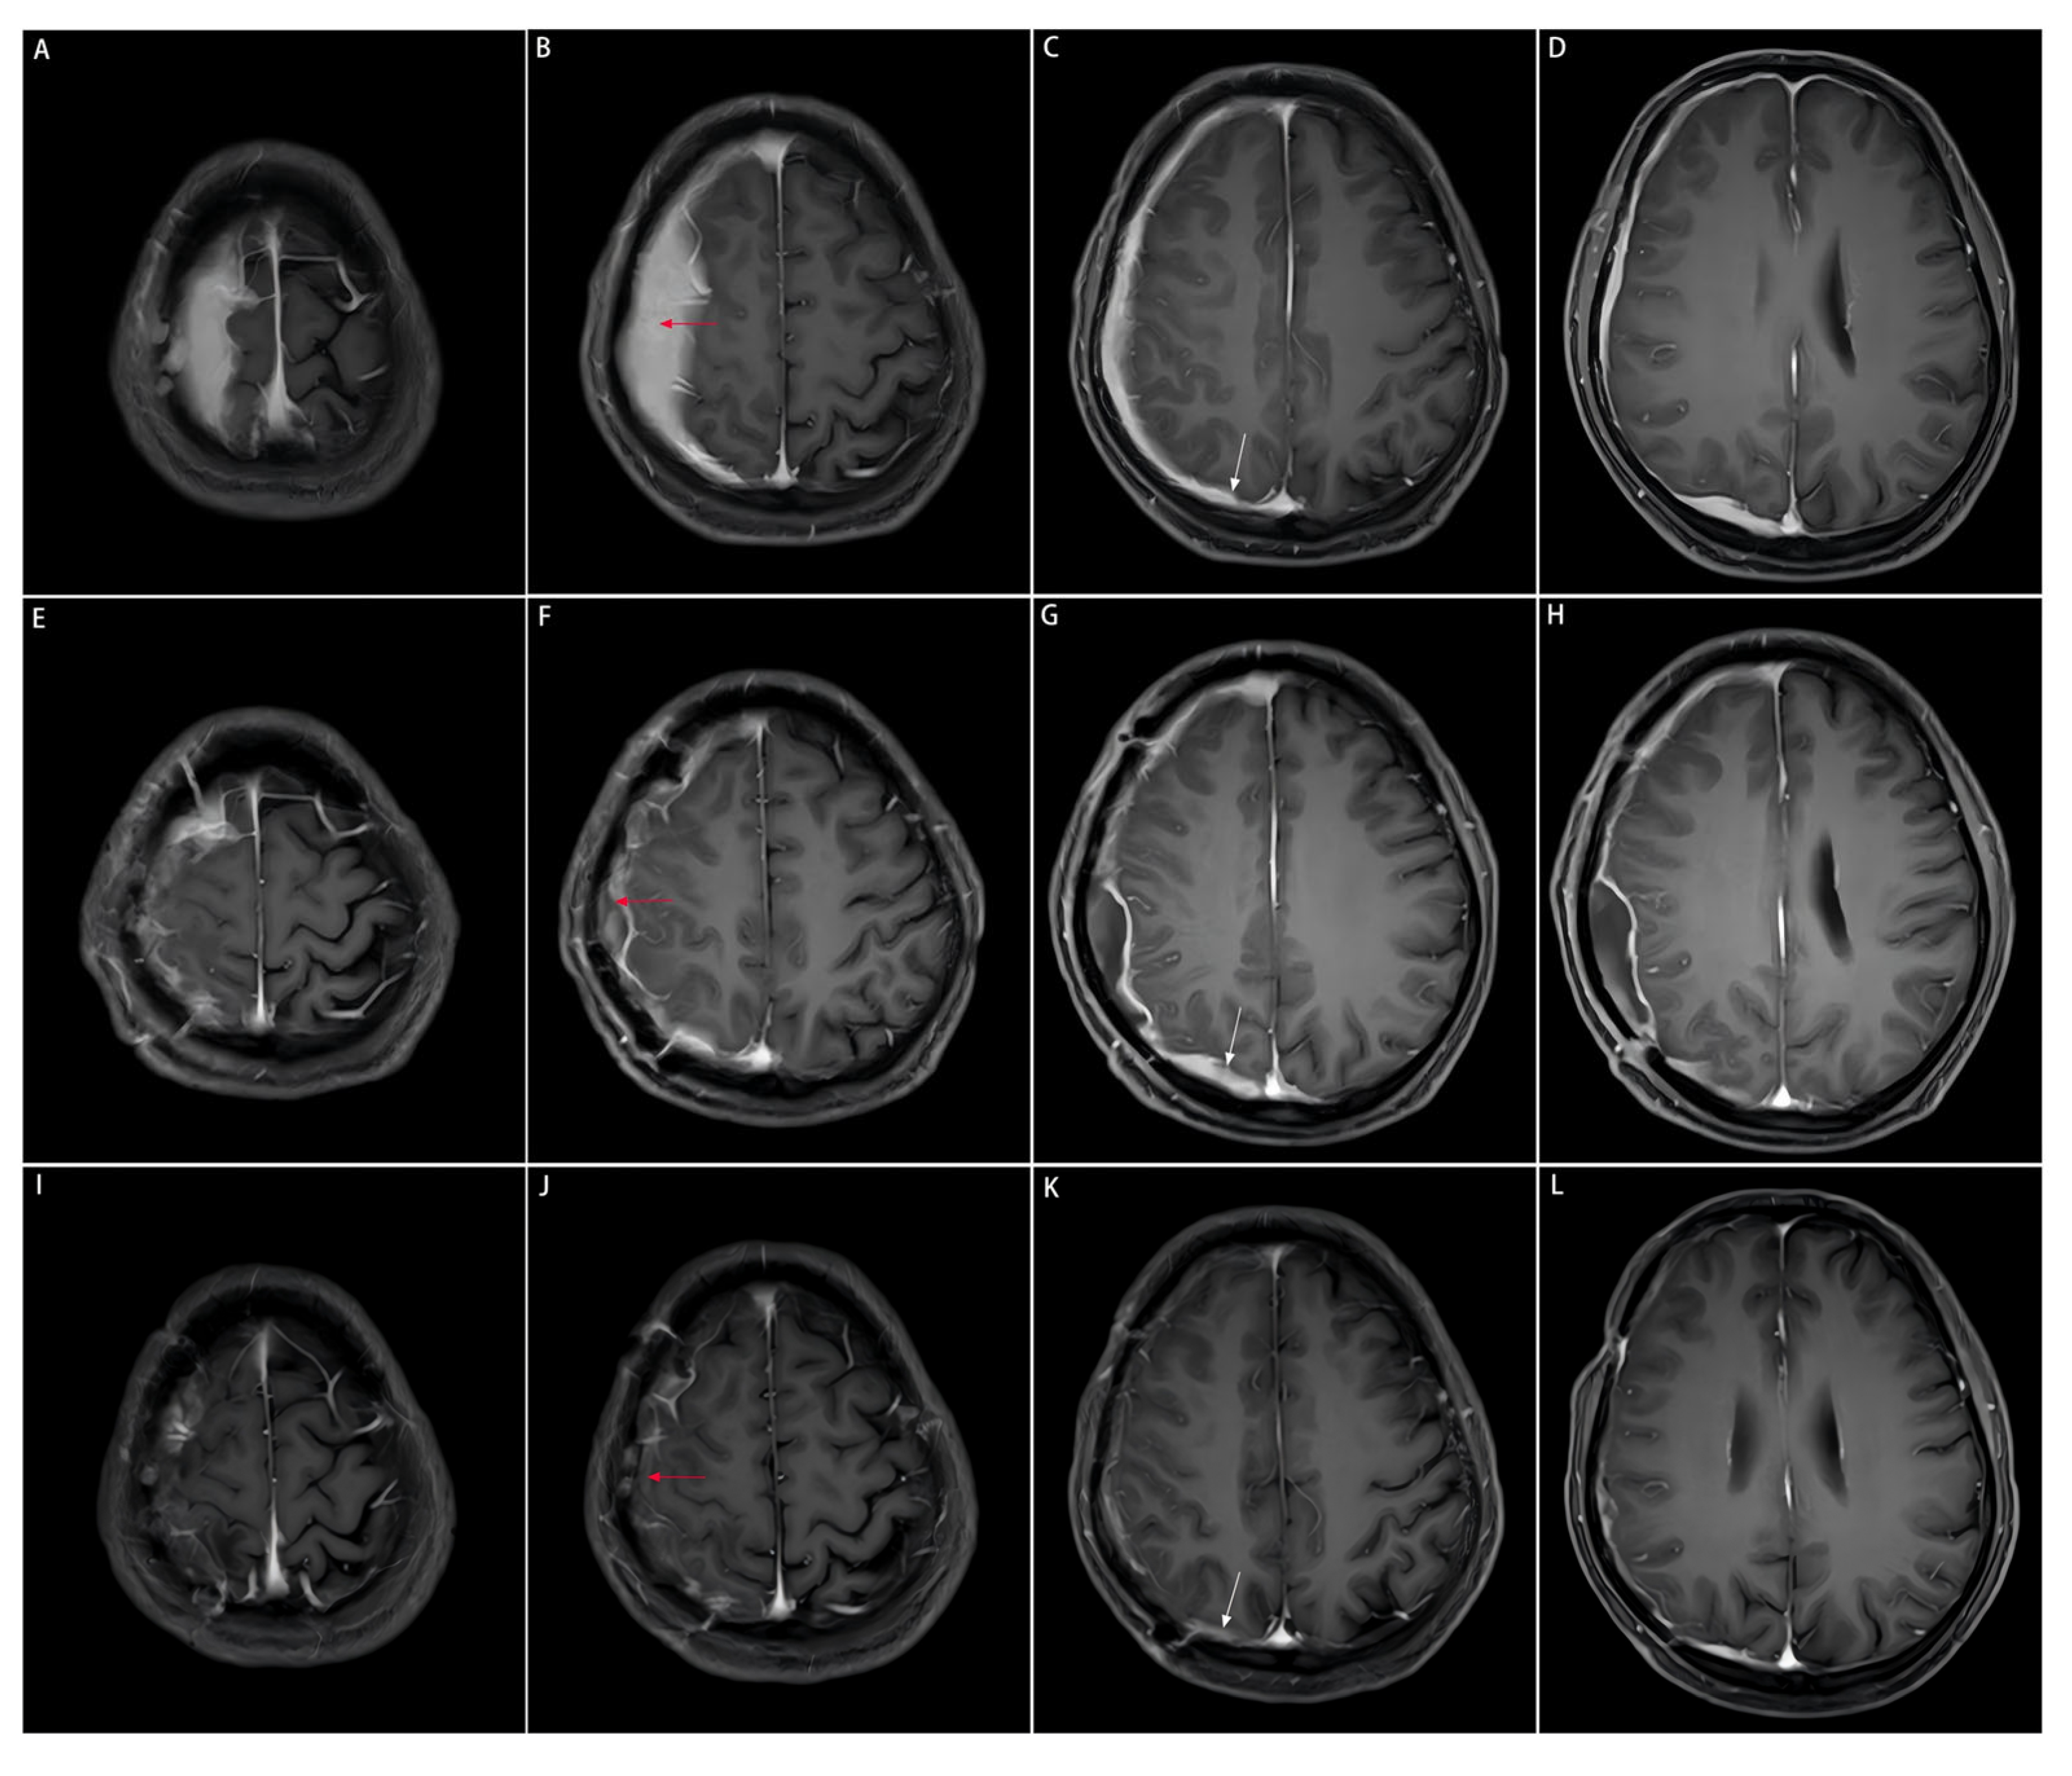

Head computed tomography (CT) scans (Philips Healthcare, Best, the Netherlands; software version R5.3) displayed a soft-tissue mass with a Hounsfield unit (HU) of 44, manifesting as a slightly high-density shadow in the right frontal lobe underneath the parietal bone, and compressed adjacent brain tissues (Figure 1A,B). Destruction of the right parietal bone was also seen on CT scans (Figure 1C,D). Nodular and strip-shaped thickening, uniform dural enhancement at the top of the right frontal, temporal and parietal lobes, and a spindle-shaped mass under the scalp with an abnormal cranial plate signal were found on preoperative contrast-enhanced magnetic resonance imaging (MRI) scans (Philips Healthcare, Best, the Netherlands; software version R6.1) (Figure 2A–D).

Figure 2.

Comparison of preoperative, postoperative, and post-medication enhanced-contrast MRI images. The area of the resected dural mass before and after the subtotal resection, and after medication on enhanced-contrast MRI images is indicated by the red arrow. The dural mass close to the cerebral falx on enhanced-contrast MRI images is indicated by the white arrow. This part is not surgically removed due to the tricky localization approach to the midline, but significantly shrinks after the three-month medication of prednisone acetate. (A–D): Enhanced-contrast MRI images preoperatively, (E–H): 2 months postoperatively, (I–L): 3 months of prednisone acetate.

The patient was postoperatively medicated with prednisone acetate (60 mg/d), calcium supplements and proton pump inhibitors to prevent complications. The follow-up imaging at 3 months postoperatively showed a significant reduction in diffuse meningeal thickening and enhancement, suggesting a sensitive response of IgG4-RHP to glucocorticoid therapy (Figure 2I–L).